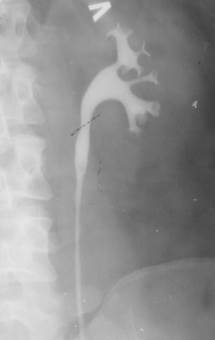

| Рис. 6.4. Ретроградная пиелография слева. Более контрастное изображение чашечек, лоханки по сравнению с экскреторной урограммой. Норма. |